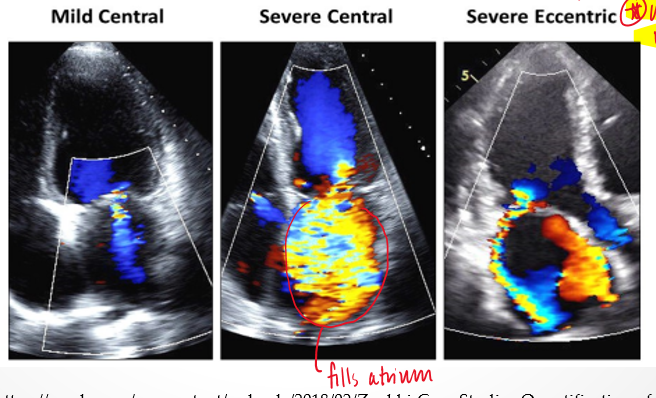

PISA is more accurate for what type of jets/orifice?

jets : central

orifice : circular

(holosystolic MR)

what is an eccentric jet?

travels along atrial wall

how does the severity of the mitral valve regurgitant jet change when it it eccentric?

severity is underestimated because energy dissipates when jet touches other structures

what is the coanda effect?

loss of momentum of eccentric reurgitant jet